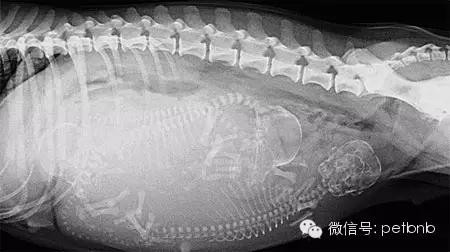

(孕后期的X光片,能够清楚看到狗宝宝和狗妈妈的骨骼)

通过X光或者B超能够清楚的看到狗狗孕育着几只狗宝宝。这样就不会发生主人以为狗狗已经生产完毕,但是其实还有小狗没出生的情况,这种情况通常会比较危险,母犬的体力耗尽,很容易疏于照顾,弄伤新生的幼崽。

难产风险比较高的狗狗,也能够清楚的看到母犬的骨盆大小和胎儿的头骨尺寸是否匹配,判断难产的可能性。